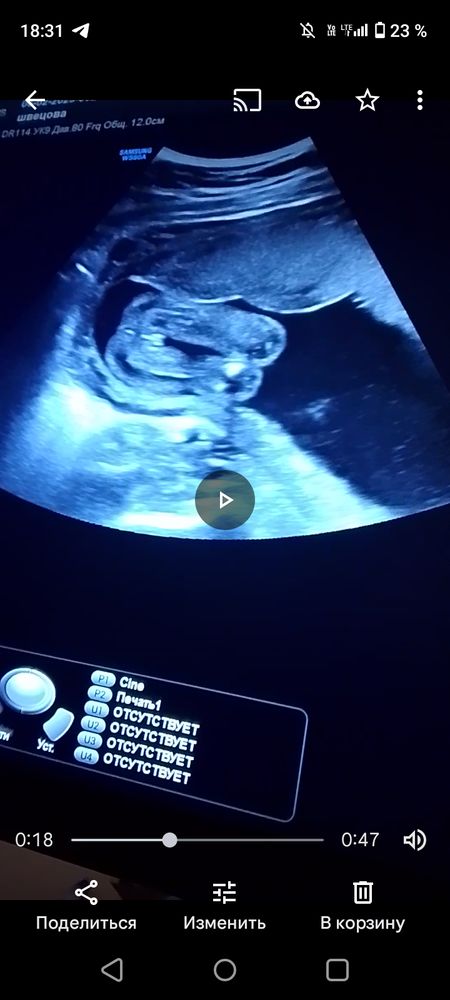

На какой неделе по узи сказали пол?

Пол малышаМне оба раза в 12 недель на скрининге правильно предположили. Сейчас я хочу на 23 февраля сделать гендер - пати. Будет 15 полных недель и два дня. Могу ли я в 15 ровно 21 февраля сходить на узи по определению пола? В 16 недель ходила с обоими детьми и видели хорошо пол. А в 15 увидят!?